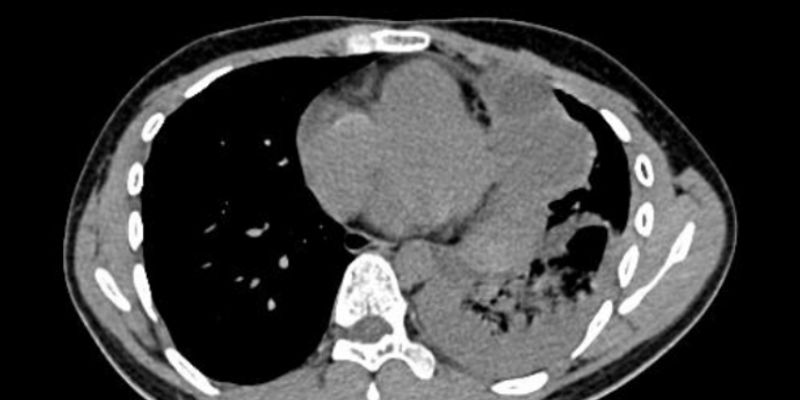

本文深入解析梅奥诊所如何通过多学科协作(MDT)成功治疗一例罕见、危及生命的甲状腺癌晚期病例。该肿瘤侵犯了患者的心脏和气道,治疗难度极高。了解复杂癌症的治疗挑战、MDT模式的优势以及国际顶尖医疗机构的集成护理能力,为患者寻求最佳治疗方案提供参考。 Read More... "罕见甲状腺癌侵犯心脏气道:梅奥诊所MDT团队如何成功挑战复杂手术与治疗方案"